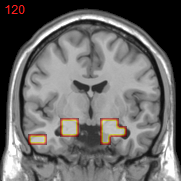

Figure 2: Feature selection by different models. The top row illustrates selected voxels in a 3D model (voxels with positive β𝛽\beta are in brown and negative ones are in blue), the mid and bottom rows illustrate the corresponding projections on brain slices.

Feature selection. For each task, the selected features are those whose β𝛽\beta are not zero . In Figure 2, the result of 30ADNC is used to illustrate the feature selection by different models (using the parameters at their best accuracy). As shown, the selected voxels by both GFL and n2superscript𝑛2n^{2}GFL cluster into several spatially connected regions, whereas those of lasso and T-test/MLDA scatter around. Also, as mentioned before, the LapL tends to select much more voxels than necessary due to the l2subscript𝑙2l_{2} regularization. Moreover, the selected voxels by GFL and n2superscript𝑛2n^{2}GFL are concentrated in Hippocampus, ParaHippocampal gyrus (which are believed to be the early damaged regions). On the other hand, the lasso and T-test/MLDA either select less lesion voxels or select probably noisy voxels not in the early damaged regions.